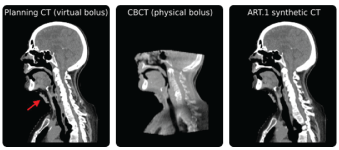

Example of a challenging case

Challenging Cases

ART.1 maintains robust image registration and dose calculation performance with challenging cases including the presence of bolus, implants, bite blocks, and artefacts.